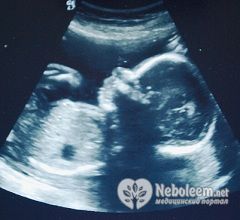

По УЗИ на 22 неделе беременности длина плода достигает 27-28 см, весит он приблизительно 430-500 г.

Врач в обязательном порядке направит женщину на УЗИ в 22 недели беременности, если она не прошла его в 20-21 неделю. Даже при благополучном течении беременности этот скрининговый метод визуализации обязателен, так как позволяет оценить состояние плода. УЗИ в 22 недели беременности позволяет не только провести фетометрию (измерить основные весо-ростовые показатели плода), но и определить пол, степень созревания и толщину плаценты, более мелкие пороки развития.